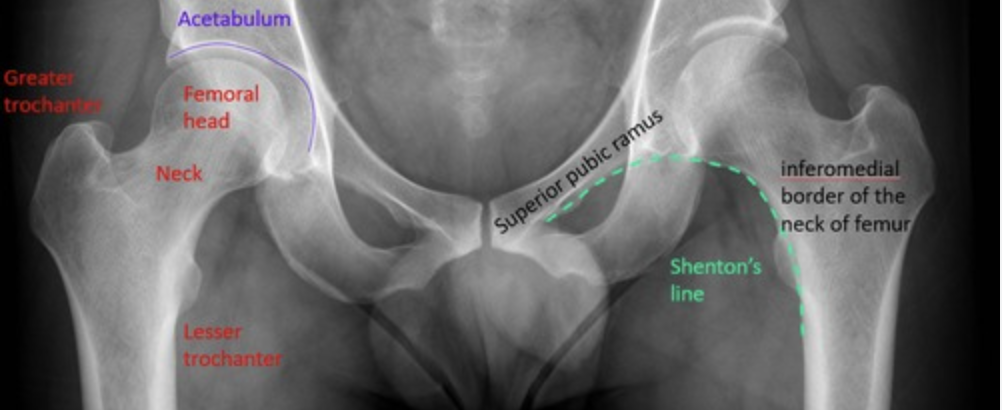

What is the line called that can be used to diagnose NOF fractures on x-ray?

A

Shenton’s line